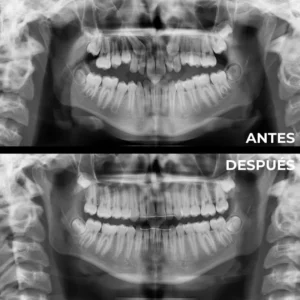

Donde realizamos una primera visita, una historia clínica, tomamos una serie de fotos extra e intraorales y realizamos unas radiografías para poder con toda esta información estudiar cada caso individualizado por todo nuestro equipo de profesionales.

Tomaremos unos modelos de su boca para poder realizar un diagnóstico preciso.